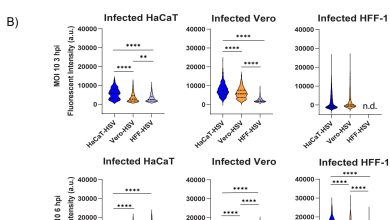

Vírus do herpes cultivados de diferentes linhas celulares exibem propriedades biológicas distintas, a pesquisa revela

O HACAT-HSV produz mais proteínas virais no início da infecção. Crédito: Journal of Virology (2025). Doi: 10.1128/jvi.00829-25 Matthew Taylor comparou…